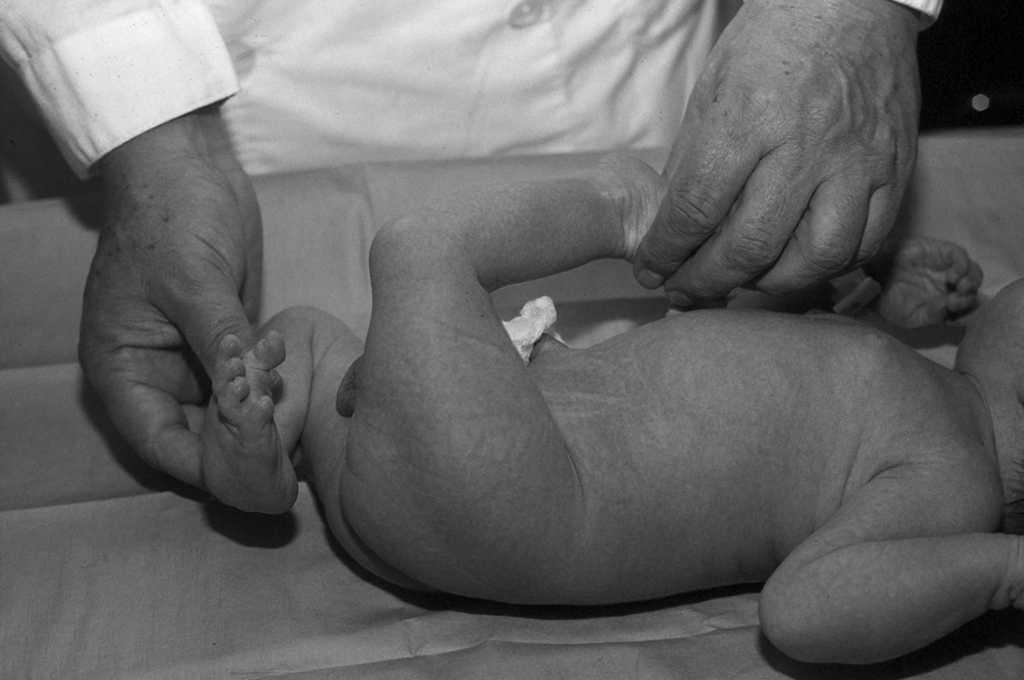

Figura 3. Fractura supracondílea femoral tras un intento de reducción de la luxación congénita de rodilla.

En cuanto a las complicaciones, la más frecuente fue la fractura de tibia en 3 pacientes (4 rodillas), siendo en un caso bilateral. Un paciente sufrió una fractura de fémur (fig. 3). Tres pacientes (4 rodillas) presentaron al final del tratamiento un leve recurvatum en la tibia y un paciente (una rodilla) en la tibia.

En cuanto a las complicaciones, la más frecuente fue la fractura de tibia en 3 pacientes (4 rodillas), siendo en un caso bilateral. Un paciente sufrió una fractura supracondílea de fémur. Pensamos que fue debido a una manipulación excesivamente intensa al inicio del tratamiento. Hay muy pocas series en la literatura actual que recogen esta complicación. Jacobsen13 presenta fracturas de fémur o de tibia en el 30% de los pacientes, porcentaje sensiblemente superior al recogido en nuestro estudio (25%).